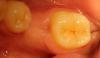

METT Опубликовано 13 апреля, 2013 Автор Поделиться Опубликовано 13 апреля, 2013 Давно не выкладывал-еще фото.46-пломба-дефект-кариес I-II кл медиодистально,на момент обращения у меня фотика не было,пришлось снять только точево и вкладку. Ссылка на комментарий

METT Опубликовано 13 апреля, 2013 Автор Поделиться Опубликовано 13 апреля, 2013 17,на 2-3 снимке на дне sdr Ссылка на комментарий

METT Опубликовано 13 апреля, 2013 Автор Поделиться Опубликовано 13 апреля, 2013 16 Ссылка на комментарий